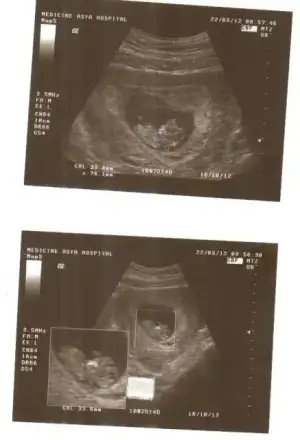

bu arada kızlar ultrason resimlerinizi koysanıza bakalım :nazar: :nazar: hatta topik açılsa göbişler ve ultrason resimleri ile ilgili çok iyi olur :31:

Ben koyuyorum resim ama başka kimsenin yoktuğu yok anneler çok üşenceç olmuyor ama böyle ya

bende koyuyorum hatta bu sabah yine gittim biraz kanama bölgesi görüldü ama bebişim gayet iyiydi :nazar: :nazar:

diğer annişleri de bekliyoruz :46: